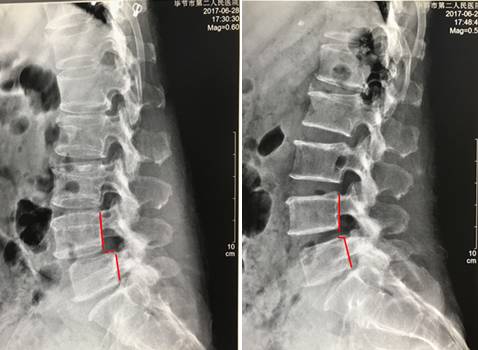

典型案例